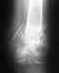

Надо посмотреть на снимок. Если нагрузку советуют ограничить, для этого возможно множество причин в Вашем случае, которых не было в обсуждавшемся. Может, получилась не очень стабильная фиксация, или запирающие винты небольшого диаметра, или их мало, или линии перелома проникают в сустав, или мало ли почему еще.